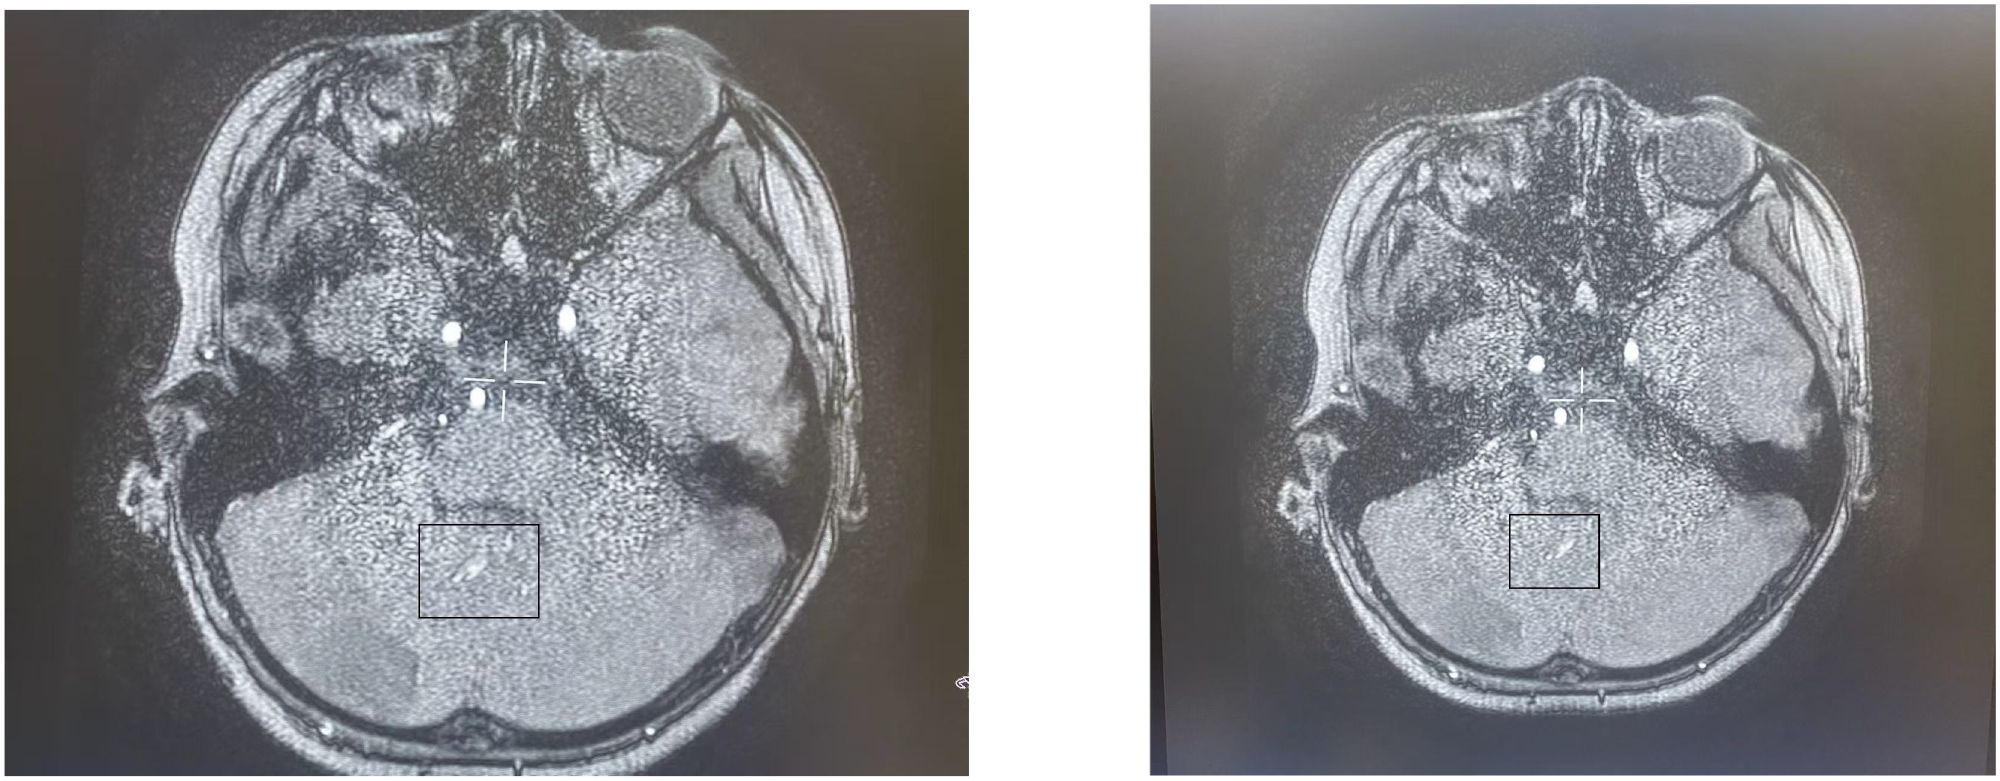

Objective This case report presents a pediatric case of eosinophilic granulomatosis with polyangiitis (EGPA) presenting with cerebella infarction as the initial symptom. The study aims to summarize the clinical features and treatment advancements of this condition, enhancing clinicians 'understanding and reducing misdiagnosis and missed diagnosis. Methods A 9-year-old male patient admitted to the Rheumatology Department of Anhui Provincial Children's Hospital was evaluated for "Dizziness, vomiting for one day, and consciousness impairment for half a day." The patient had recurrent bilateral lower limb rashes and asthma attacks over the past year. Blood tests revealed elevated eosinophil levels and IgE antibodies, while bone marrow cytology showed increased eosinophil counts. Brain MRI demonstrated cerebral infarction, herniation, and suspected thrombosis, with skin biopsy confirming vasculitis characteristics. Through retrospective analysis of clinical data and literature review, this study comprehensively summarizes EGPA's clinical features and treatment progress. Results The patient presented with cerebella infarction as the initial symptom, accompanied by central nervous system involvement, skin manifestations, hematological disorders, and vasculitis. With a history of asthma attacks, eosinophil counts during hospitalization peaked at 4.9×10^9/L (compared to baseline levels>1×10^9/L). After thorough evaluation for infections, malignancies, diffuse connective tissue diseases, immunodeficiency disorders, and inherited metabolic disorders, EGPA was confirmed. Treatment included anti-inflammatory steroids, cyclophosphamide (CTX) induction therapy, anticoagulation, followed by mycophenolate mofetil (MMF) maintenance at therapeutic doses, supplemented with rituximab. Current follow-up shows normalized eosinophil counts, restored muscle strength, resolution of skin rashes without recurrence, and favorable clinical response. Conclusion EGPA presents diverse clinical features. Cerebella infarction as the first neurological manifestation in children is rare. Eosinophilia serves as a characteristic feature. When pediatric asthma patients exhibit neurological symptoms, EGPA should be considered. For cases with central nervous system involvement, combined steroid therapy with cyclophosphamide pulse induction proves effective.